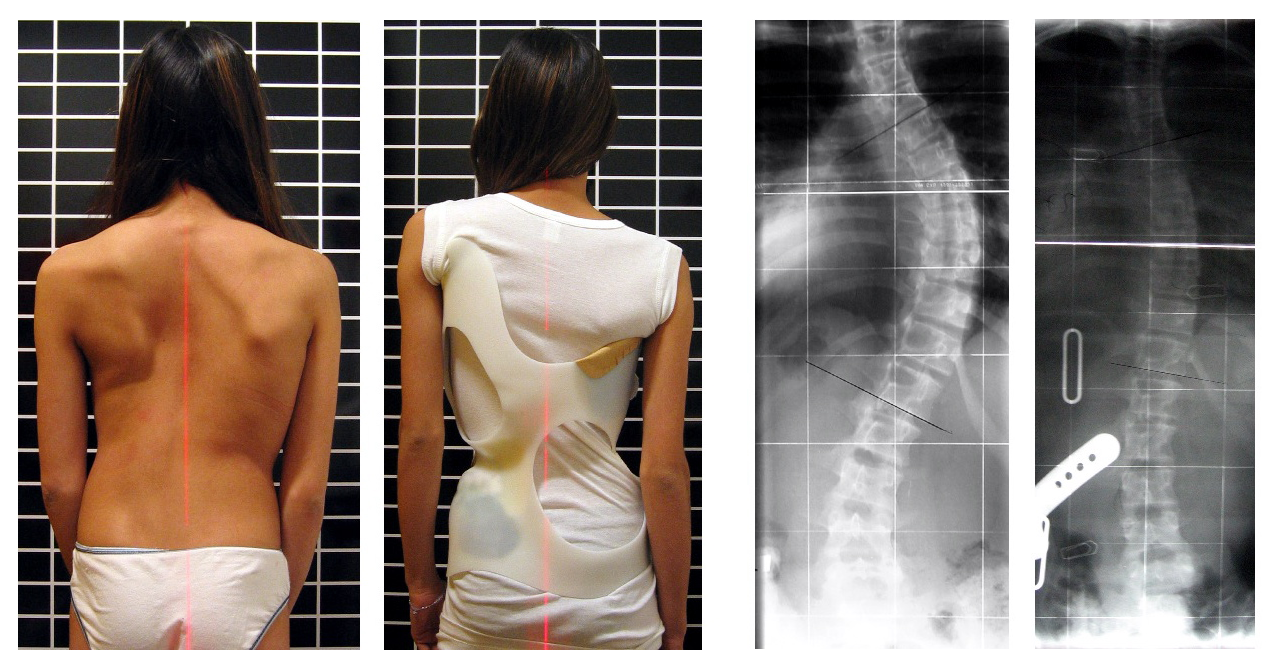

Severe scoliosis or left untreated can look like this:

According to the Scoliosis Research Society, 85 percent of all scoliosis causes are idiopathic, meaning the cause is unknown. The remaining causes of scoliosis include birth defects, such as vertebrae that form abnormally before birth, and certain disorders such as cerebral palsy, Marfan’s syndrome, muscular dystrophy and Down syndrome. Infections and spinal fractures can also cause scoliosis.curvature of the spine during surgical correction of this condition. Screws and rods are placed in order to stabilize and straighten the spine.

- Dextroscoliosis describes a spinal curve to the right (“dextro” = right). Usually occurring in the thoracic spine, this is the most common type of curve. It can occur on its own (forming a “C” shape) or with another curve bending the opposite way in the lower spine (forming an “S”).Symptoms of scoliosis include an uneven waist, uneven shoulders, disjointed hip and a protruding shoulder blade, according to Mayo Clinic. The spine also curves or twists in acute cases, and the disease can cause one side of the ribs to protrude more than the other. Severe cases also induce labored breathing and back pain.Scoliosis can be recognized and diagnosed with a clinical exam, but xrays are necessary to fully evaluate the magnitude and type of scoliosis present. For a proper scoliosis evaluation, full length, whole spine xrays need to be performed. An MRI may also be recommended if there are symptoms of leg pain that may be associated with stenosis or if there is concern about possible spinal cord compression or abnormalities.

The treatment of adult scoliosis is very individualized and based on the specific symptoms and age of the patient. Many patients have scoliosis and have very minor symptoms and live with it without treatment. Patients with predominant symptoms of back pain would typically be treated with physical therapy. Patients with back pain and leg pain may receive some benefit from injection treatment to help relieve the leg pain. If lumbar stenosis (narrowing of the spinal canal) is present and is unresponsive to non-surgical treatment, then a decompression( removal of bone and ligaments pressing on the nerves) may be recommended. If the scoliosis is greater than 30 degrees, a fusion procedure will most likely be recommended along with the decompression. The fusion is recommended to prevent the curve from progressing when the spine is destabilized by the bone removal that is necessary to decompress the nerves. Fusions are usually accompanied with metal rod and screw placement into the spine to help correct and stabilize the scoliosis and help the bone heal or fuse together. The length of the fusion, or the number of spine levels included, depends on the type of scoliosis and the area of the spine involved. The goal of adult scoliosis surgery is to first remove pressure on the nerves, and second to keep the scoliosis from progressing further.